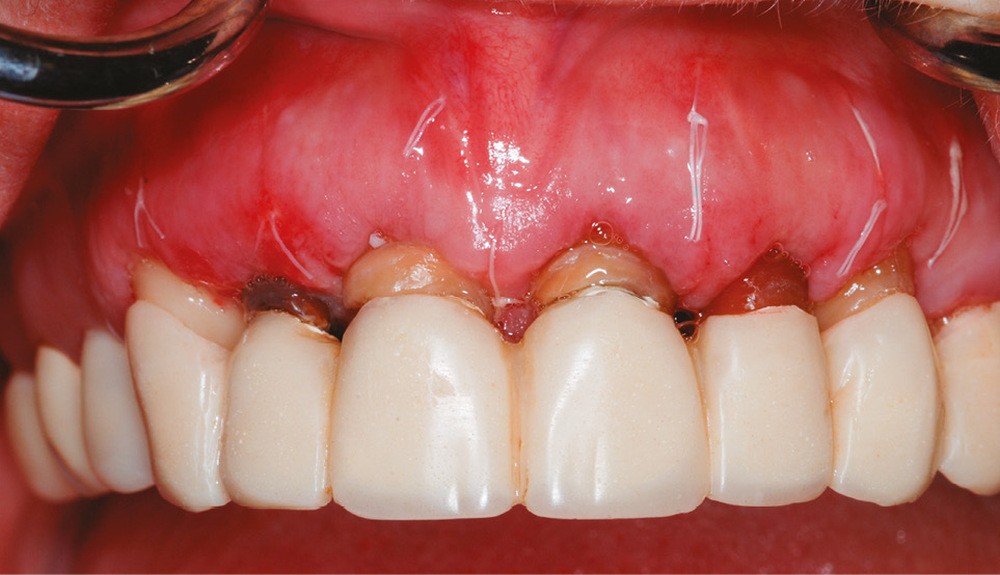

1 – Le système d’attache d’une dent est composé de l’os alvéolaire, du ligament alvéolo-dentaire et de l’attache épithélio-conjonctive ou attache supra-crestale. L’attache supra-crestale, anciennement confondue avec l’espace biologique, est un espace d’environ 2 mm [1] occupé par l’attache conjonctive (1 mm) et l’attache épithéliale (1 mm). Il est normalement visible à la radiographie rétro-alvéolaire entre le sommet de la crête osseuse et la jonction émail-cément. Comme une dent possède naturellement un sulcus, certains auteurs estiment qu’il convient d’y ajouter au moins 1 mm de sulcus libre de toute structure prothétique [2]. On peut donc considérer l’espace biologique comme un « espace clinique sanctuarisé » de 3 mm au sommet de la crête osseuse alvéolaire, nécessaire à la santé et à la stabilité parodontale. La violation de l’espace biologique génère un traumatisme parodontal aboutissant à des récessions gingivales ou des gingivites prothétiques (fig. 1a-b).